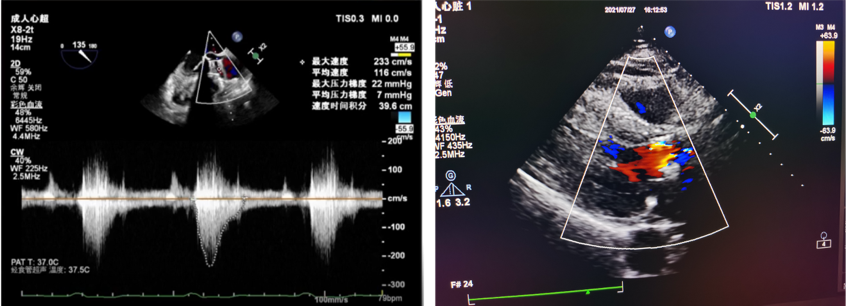

超声检查

心脏彩超:1、主动脉瓣置换后生物瓣重度狭窄合并重度关闭不全;主动脉瓣瓣口流速Vmax 4.24m/s,峰值跨瓣压差72mmHg,平均跨瓣压差36mmHg,瓣环内径20.9mm,升主34.2mm。2、左房增大;3、升主动脉增宽;4、室间隔增厚;5、二尖瓣、三尖瓣及肺动脉瓣返流(轻度);6、左室舒张顺应性减退。

术后评估

主动脉瓣术后平均压差7mmHg,无瓣周漏。